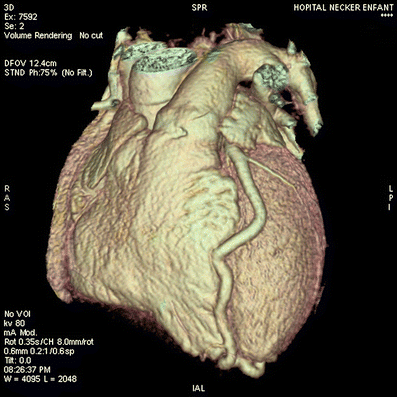

Volume-rendered reconstruction of the whole heart shows a tortuous and enlarged left coronary artery that descends between the ventricles to the apex